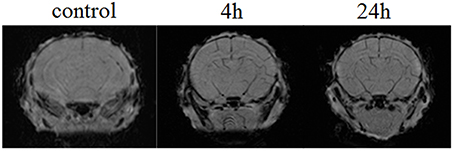

Figure 4 demonstrates the example of MRI-results in SWI regime obtained from 10 newborn rats in each group (the control, pre- and post-hemorrhage). The pre- and post-hemorrhage periods were characterized by hypointense contrasting of cerebral vessels. These changes can be caused by the accumulation of deoxyhemoglobin due to prolonged hypoxia leading to reduced oxygen levels.

Figure 4. The example of MRI-SWI image of neonatal rat brain in normal state (the control group, n = 10), in the pre-hemorrhage period (4 h after stress, n = 10) and post-hemorrhage period (24 h after stress, n = 10).